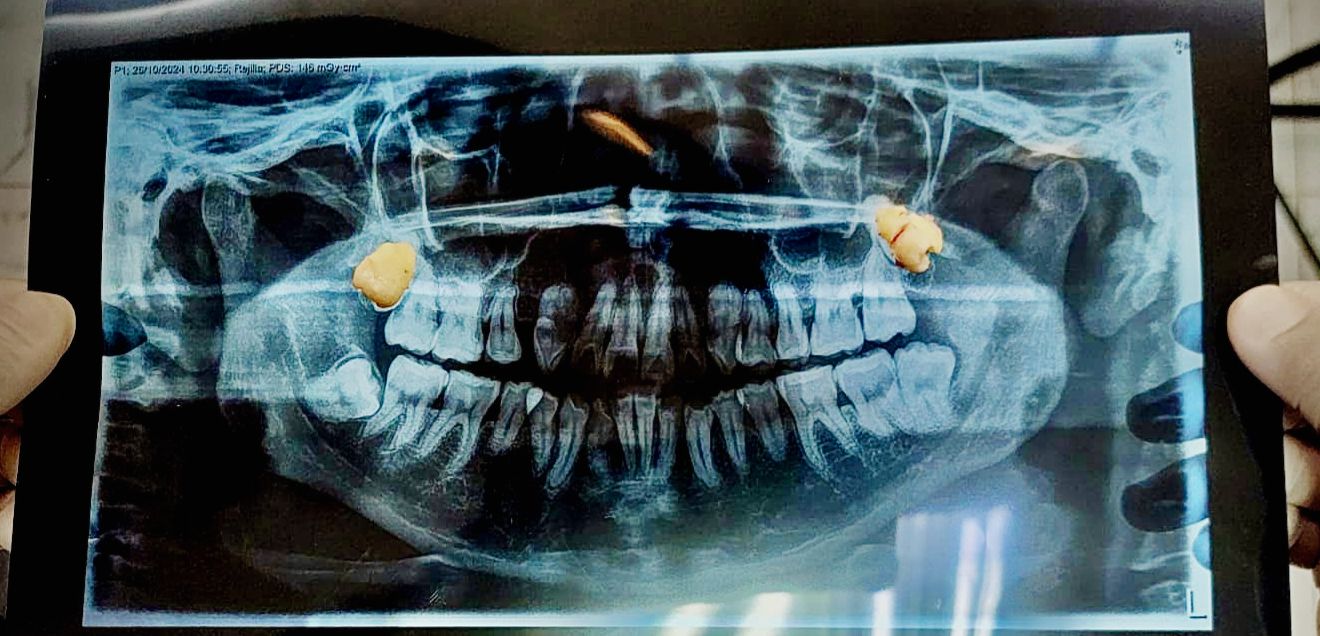

La extracción dental es un procedimiento odontológico que consiste en la remoción de un diente de su alveolo en el hueso maxilar o mandibular. Aunque se prefiere conservar los dientes siempre que sea posible, en algunos casos es necesario extraerlos para mantener la salud bucal y evitar complicaciones mayores.

• Dientes Impactados o Retenidos

• Dientes Fracturados Irreparablemente